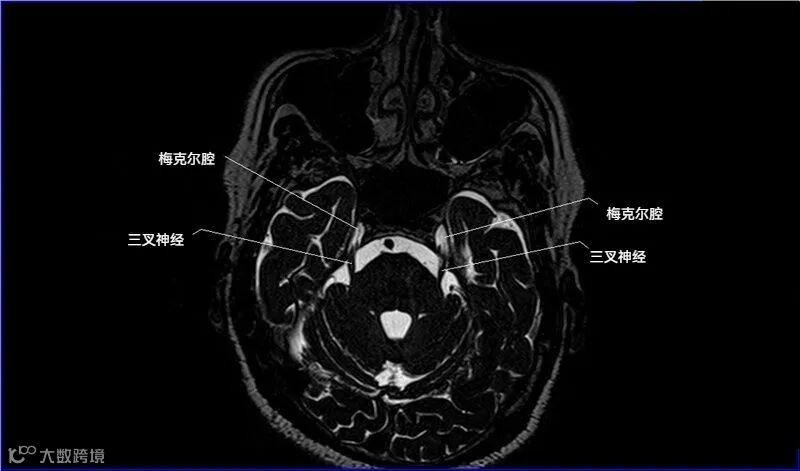

一嗅二视三动眼,四滑五叉六外展,

七面八听九舌咽,迷走及副舌下全。